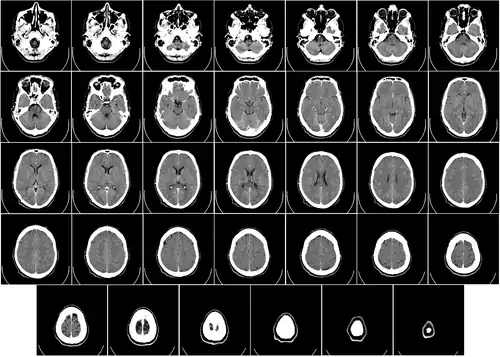

![]() Computed tomography of human brain, from base of the skull to top. Taken with intravenous contrast medium. | |

Computed tomography of the head uses a series of X-rays in a CT scan of the head taken from many different directions; the resulting data is transformed into a series of cross sections of the brain using a computer program.[1] CT images of the head are used to investigate and diagnose brain injuries and other neurological conditions, as well as other conditions involving the skull or sinuses; it used to guide some brain surgery procedures as well.[2] CT scans expose the person getting them to ionizing radiation which has a risk of eventually causing cancer; some people have allergic reactions to contrast agents that are used in some CT procedures.[2]